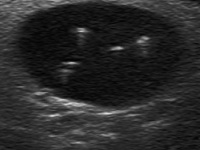

Comet-tail artifacts or colloid crystals

The so-called comet-tail artifact is very similar to the microcalcification, it is similarly bright, the size is in the range of microcalcification, although tends to be larger and occasionally exceeds 1 cm. The shape of a colloid crystal is in most cases round, however linear form is not a rare exception. The most important feature differentiating a comet-tail artifact from a microcalcification is the presence of a narrowing and fading tail in the former. Although colloid crystals typically appear in the cystic part of a mixed solid-cystic lesion, we must be aware that comet-tail artifact might be located even within the solid part and the differentiation of bright granules in a solid lesion is the other important differential diagnostic issue regarding hyperechogenic figures. Comet-tail artifact is generally held a protein-rich structure or a colloid crystal.

The presentation of this figure is frequently non-typical because of the lack of the dorsal tail. From a practical point-of-view hyperechogenic granules within a cystic fluid are best held as colloid crystals even if they lack the dorsal tail.

The issue is the appearance of non-typical forms within a solid nodule or within the solid part of a mixed nodule.